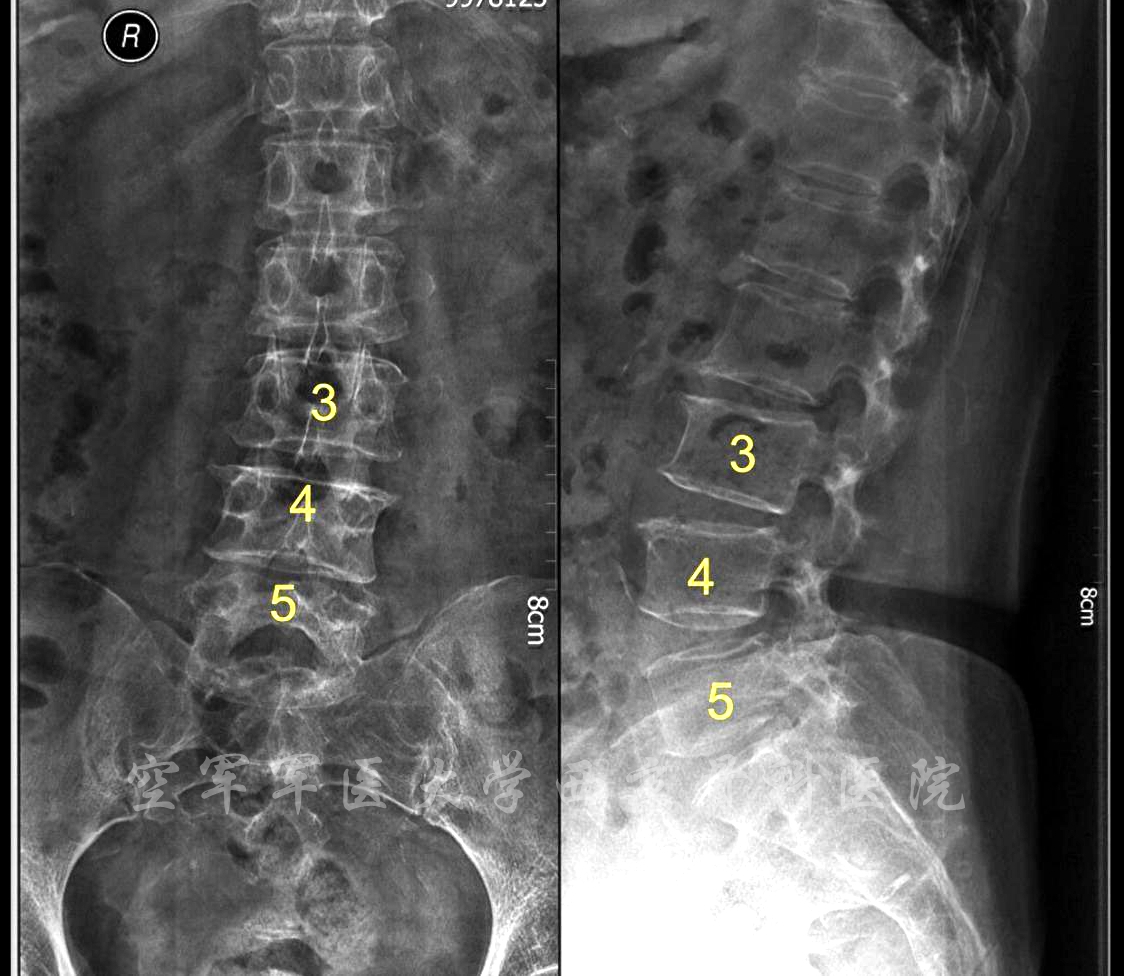

术前X线正侧位片

术前MRI

术前CT